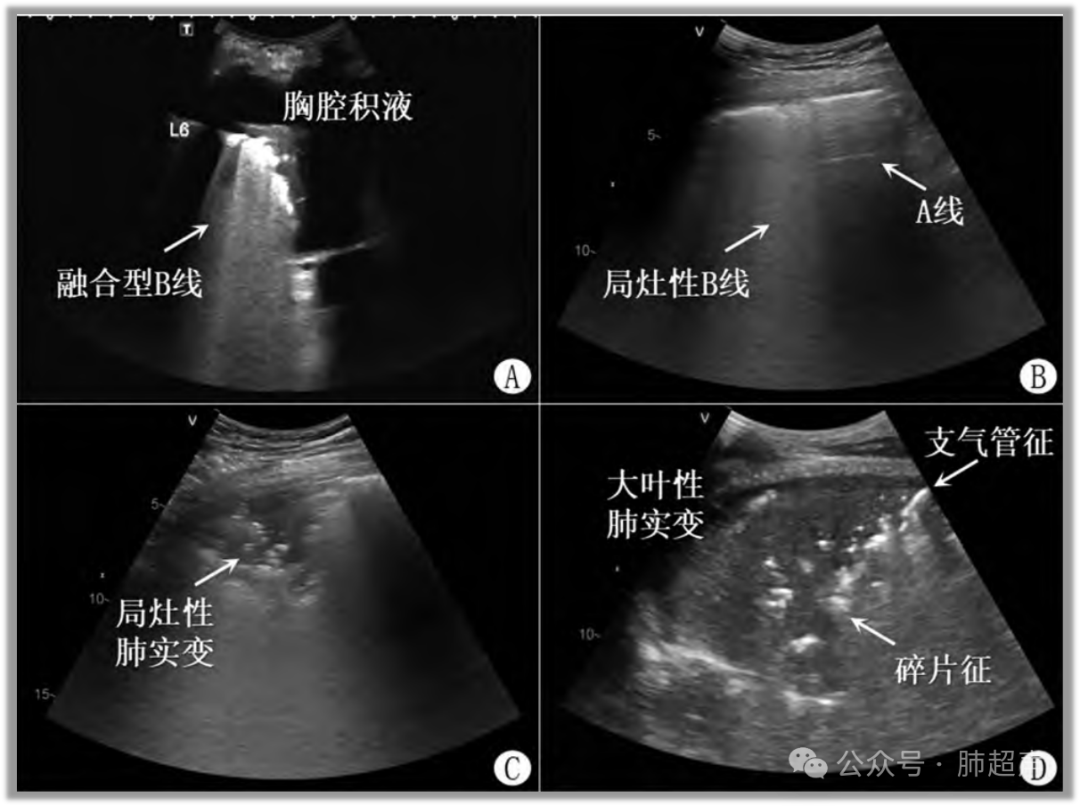

(4) 不同病原体肺炎超声表现有所不同,多发B线常见于病毒性肺炎、支原体肺炎等;大叶性肺实变常见于细菌性肺炎(图2)

图片

图2  肺炎常见超声表现

注:A. 局部肺泡炎性渗出; B. 局灶性肺炎(B线)与周围正常肺充气(A线)并存; C. 肺炎渗出不均匀,局部小范围胸膜下肺泡塌陷呈实变; D. 大范围肺叶炎性渗出呈实变。